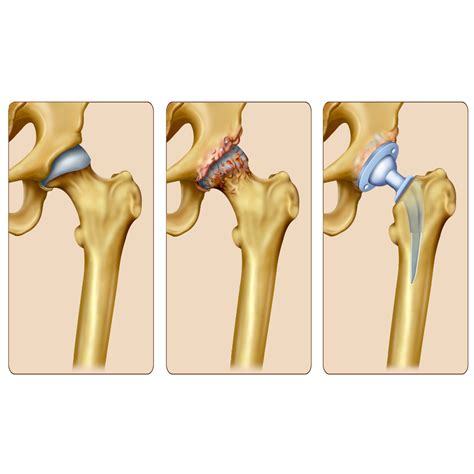

Partial Hip Replacement Surgery, also known as hemiarthroplasty, involves replacing only the damaged or diseased portion of the hip joint. Unlike total hip replacement, which replaces both the ball and socket of the hip, this procedure focuses on replacing just the femoral head (the ball part of the hip joint). This makes it a less invasive option, often preferred for certain types of hip fractures or conditions affecting only one part of the hip.

• Hip Fractures: In cases where the femoral head is fractured but the acetabulum (socket) is intact, a partial replacement can be an effective solution.

• Osteoarthritis: When osteoarthritis affects only one part of the hip joint, a partial replacement can alleviate pain and improve mobility.

• Avascular Necrosis: This condition, where the blood supply to the femoral head is disrupted, can lead to bone death and may require a partial replacement.

• Removal of the Femoral Head: The damaged femoral head is removed, and the remaining bone is prepared to accept the prosthetic implant.

• Implant Placement: The prosthetic femoral head is attached to the remaining femoral shaft using a stem. The stem can be cemented or press-fit into the bone, depending on the patient’s bone quality and the surgeon’s preference.